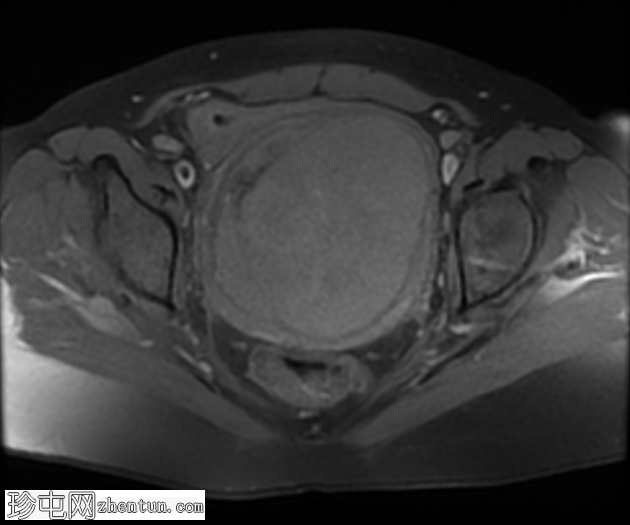

轴位

T1

宫颈后壁及子宫下段中心可见一约11.5 × 10 × 10厘米的不规则局灶性病变。该病变在T1脂肪饱和图像上呈等信号,伴有一偏心低信号区,中心有一细微高信号,提示有出血。

在T2加权图像上,病变呈中高信号,伴有囊性变性区域,以及与T1暗区相对应的偏心T2暗信号,也与含铁血黄素相符。

肿块对邻近结构产生显著的占位效应,向前压迫膀胱。膀胱呈空虚状态,Foley导尿管位于原位。